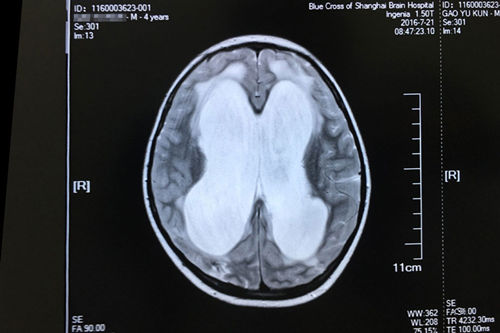

车祸昏迷74天后,亮亮来到了“蓝十字”。完善相关检查之后,神经外科主任侯增欣(政府特殊津贴专家)、原上海复旦大学附属华山医院神经外科专家潘仁龙主任,以及亮亮的主治医生副主任医师经过病情讨论会诊之后,给亮亮下的结论是:重型颅脑损伤、化脓性脑膜炎、脑积水、多发性骨折。侯增欣主任和其他专家一致认为:虽然亮亮的伤情严重,但治疗的希望还是有的。头颅MR显示:脑积水明确,各项检查完善,未见明显手术禁忌,可以开展“脑室-腹腔分流术”。

亮亮术前的磁共振影像显示:重度脑积水伴间质性脑水肿